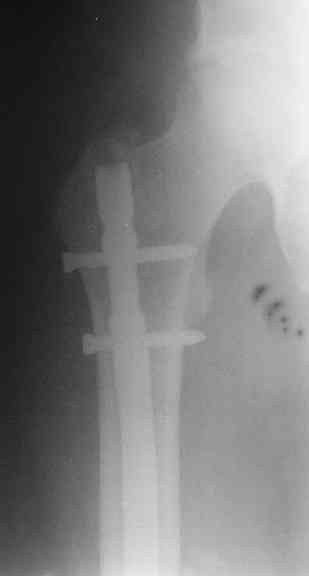

СМ> Если имеются под рукой Р-снимки, продемонстрируйте, плиз.

Вот несколько. С тисками и трубой на днях сделаем.

СМ> Что, реально изогнуть титановый гвоздь, не сломав его?

Конечно. Чтобы не сломать, лучше проложить в тиски сразу ниже отверстий полоску металла, чтобы там создалась концентрация напряжений при изгибе, а не на уровне отверстия.